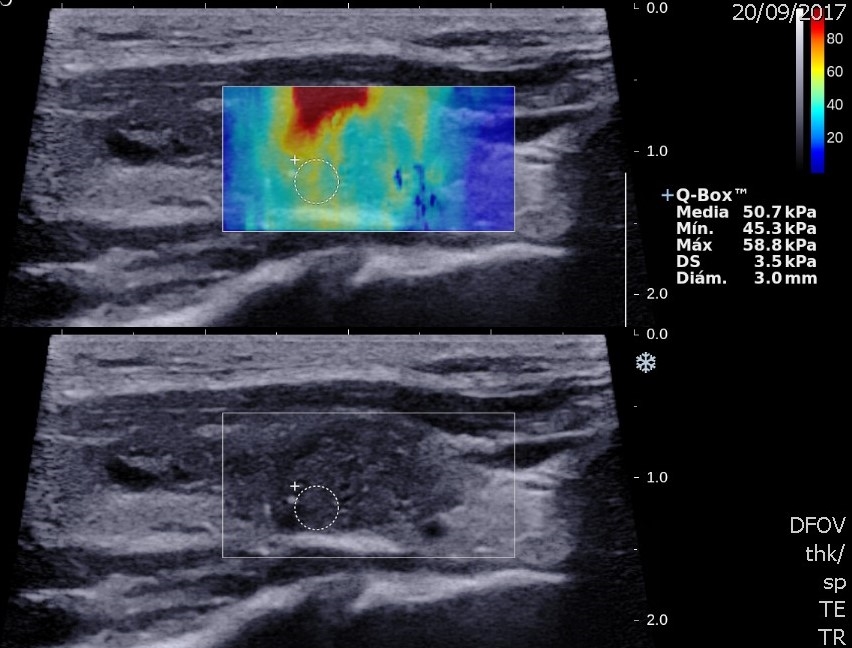

Dureza

La share wave elastography (SWE) es una nueva herramienta ecográfica que mide de manera cuantitativa la dureza o rigidez de un tejido, y reduce la subjetividad del diagnóstico clínico de la elasticidad de los nódulos. La SWE es efectiva para aumentar la sensibilidad de la ecografía en la detección de neoplasias tiroideas. Algunos autores definen al aumento de la elasticidad de un nódulo en relación con el parénquima tiroideo adyacente como mayor riesgo de malignidad. Hazem et al. establecen un valor medio para nódulos benignos de 33,46 ± 5,02 kPa y de 49,71 ± 11,16 kPa para nódulos malignos11,25. Las guías y recomendaciones de SWE publicadas por Ferraioli et al. en 2021 sugieren que los nódulos benignos muestran una elasticidad media de 15,3-28 kPa y que el punto de corte óptimo entre nódulos benignos y malignos es de 34,5-37,5 kPa26) (Figs. 21 y 22).